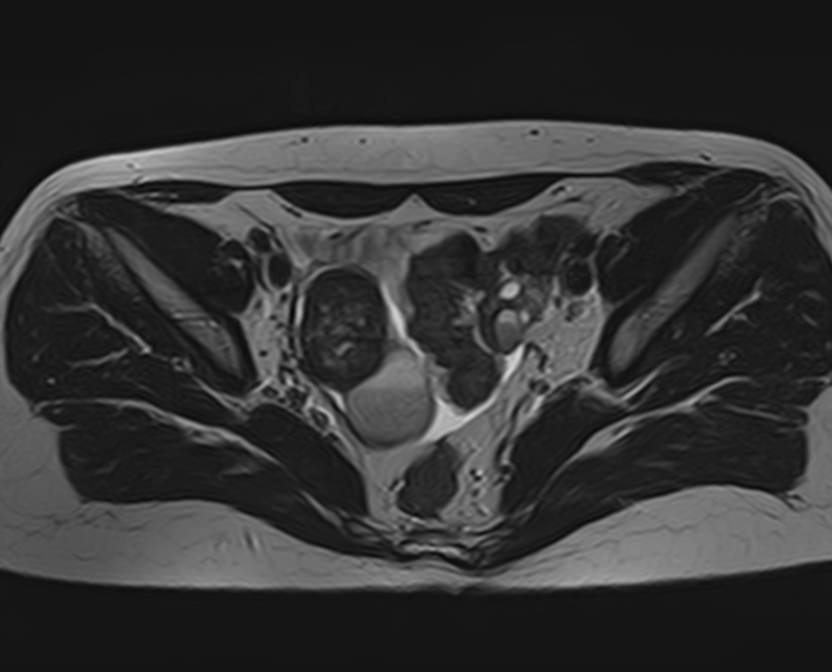

В клинике «Доступная медицина» магнитно-резонансная томография выполняется на высокопольном 32-канальном томографе последнего поколения TOSHIBA VANTAGE TITAN 1,5 Тесла, который обладает высокой разрешающей способностью и обеспечивает непревзойденное качество изображений. Аппарат производит сканирование в трех взаимоперпендикулярных плоскостях и послойными срезами с шагом от 1 мм, что позволяет визуализировать структуру органов и тканей малого таза в мельчайших подробностях. Точная и достоверная информация позволяет выявлять различные заболевания на начальной стадии, от чего напрямую зависит успех лечения.

С помощью данного исследования можно получить детальное послойное изображение матки, яичников, мочевого пузыря и мочеотводящих путей, а также жировой клетчатки, окружающей органы, и лимфатических узлов.

МРТ-сканирование органов малого таза позволяет выявить: